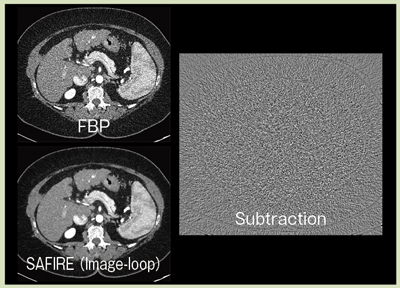

図8は,SAFIREによる画像ノイズ抑制効果を示したものである。サブトラクション画像からは,分解能を損なうことなく,画像ノイズだけが効果的に除去されている。また,SAFIREでは画像ノイズ低減後のCT画像の“テクスチャ(texture)"にも配慮がされている。非線形かつ異方性の反復型イメージベース・ノイズフィルタによって,単に物理指標としての画像SD値の改善だけではなく,処理後のCT画像があたかも高線量撮影の画像のような“ナチュラル"なテクスチャになるよう配慮がなされている。

図8 FBPとSAFIREの画像ノイズ低減効果の比較